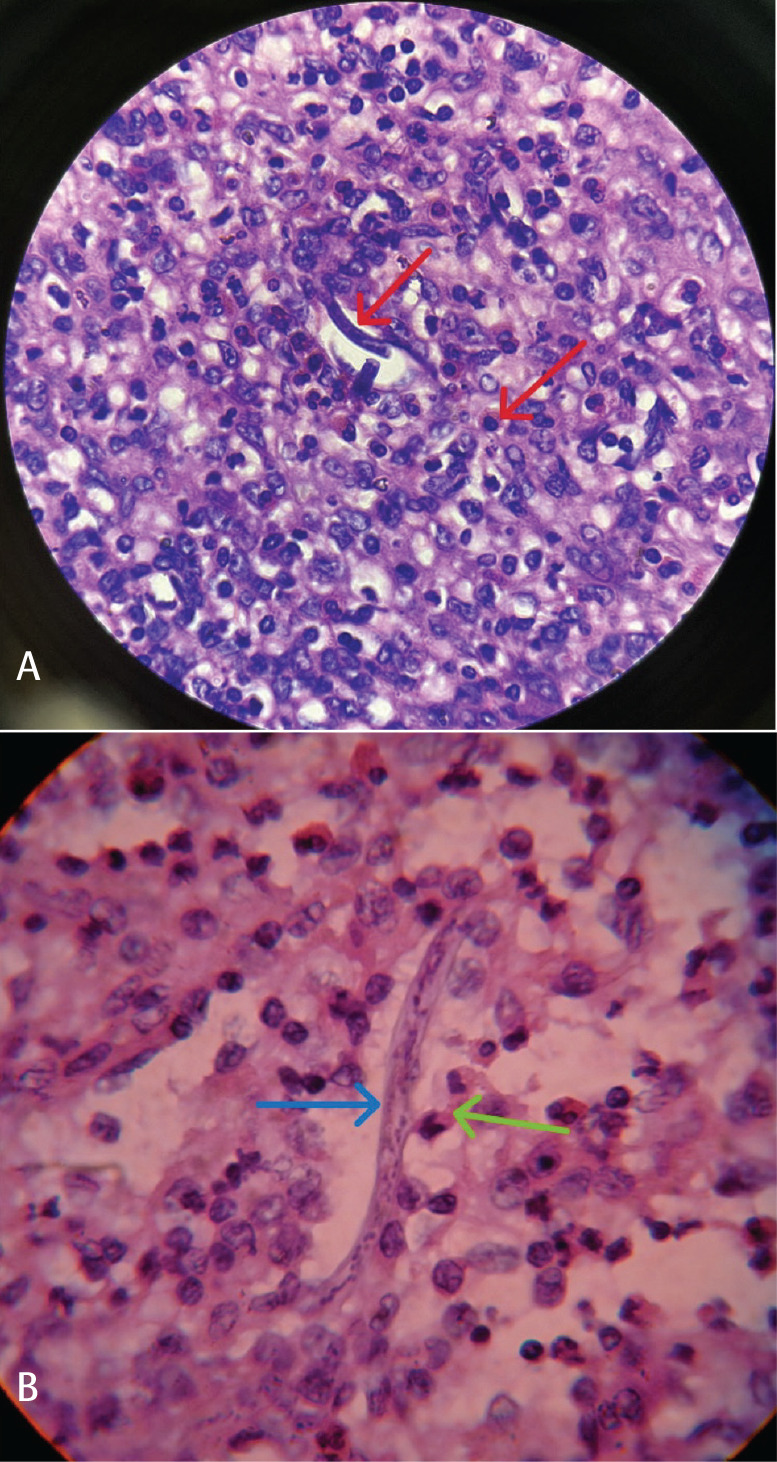

Unexpected Discoveries: Eosinophilia Masking Splenic Microfilariasis in a Young Woman